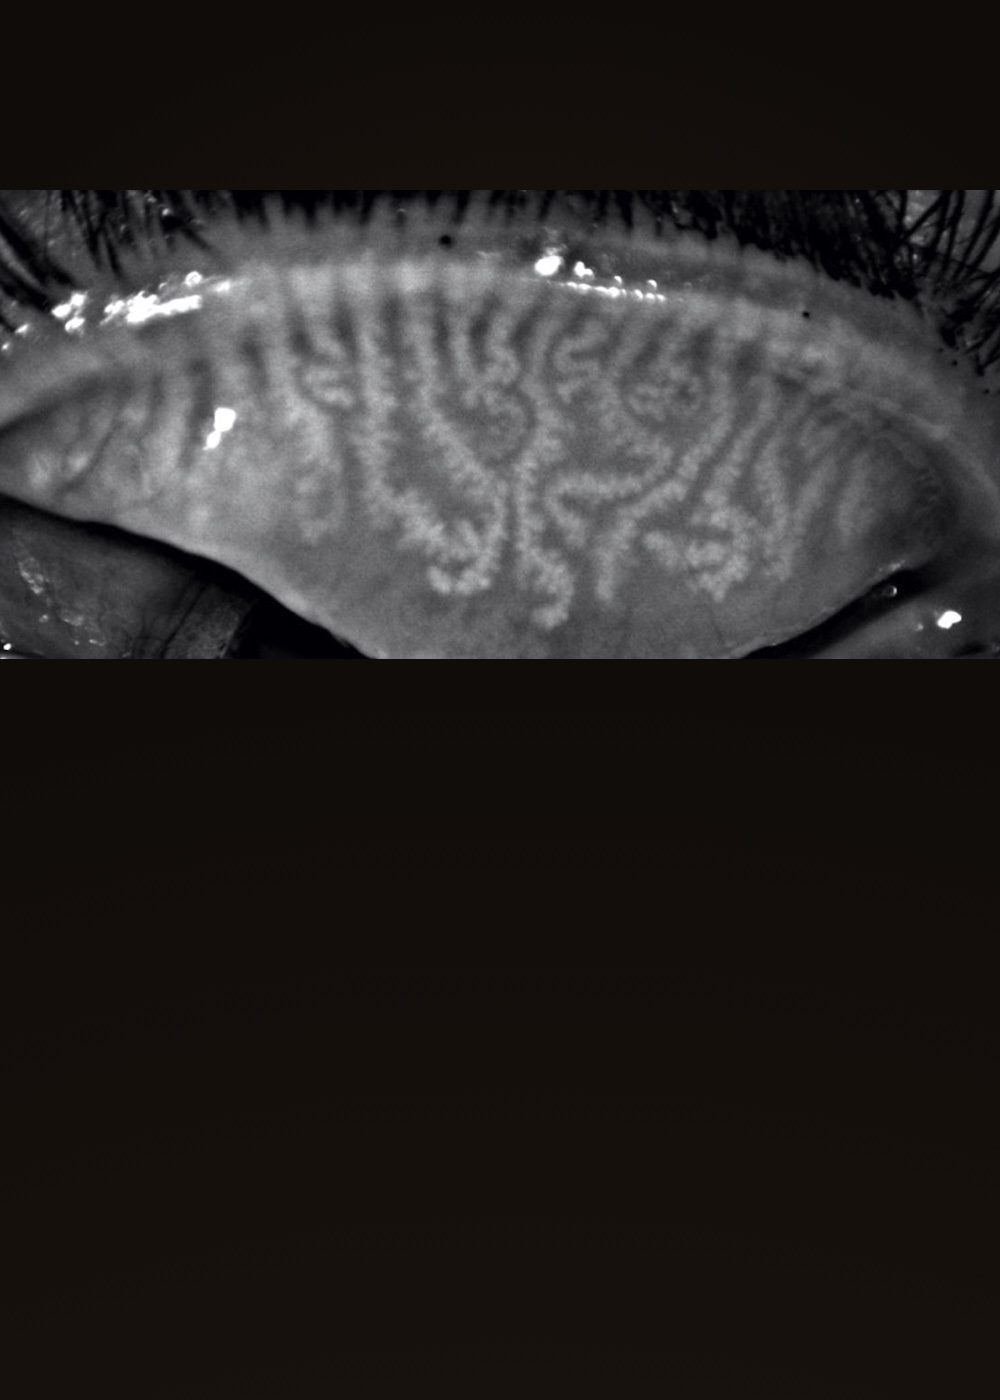

Estudio Ojo Seco

Descubre como un estudio de ojo seco puede devolverle a tus ojos el confort y la claridad que merecen